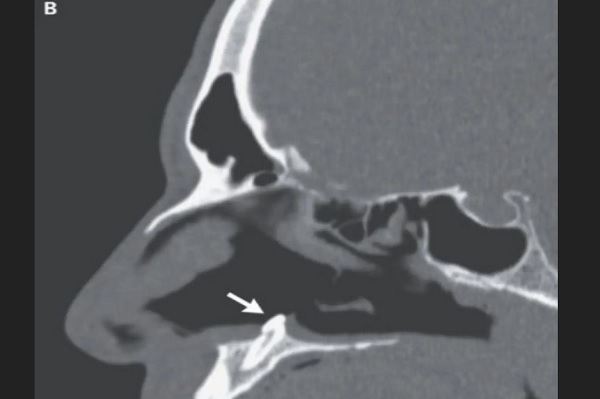

پزشکان در این مطالعه گفتند که معاینه فیزیکی این شخص، یک انحراف در سپتوم را نشان میدهد. انحرافی که دو سوراخ بینی را از هم جدا میکند. این معاینه همچنین سوراخی به طول ۲ سانتی متر در پشت سپتوم و انسدادهای کلسیفیه را نشان داد. پس از بررسیهای بیشتر مشخص شد که یک دندان در داخل بینی این شخص رشد کرده است.

دندان این بیمار که به طول ۱۴ میلی متر بود با عمل جراحی برداشته شد. پزشکان تایید کردند که مشکل تنفسی بیمار پس از معاینه و سه ماه پس از انجام جراحی به طور کامل برطرف شد.